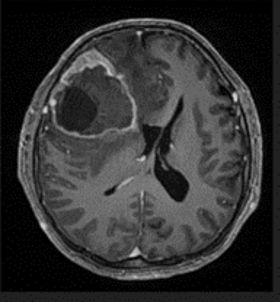

A 51-year-old male with a medical history of Neurofibromatosis type 2 presented with a clinical progression spanning 3 months, characterized by difficulties in concentration, short- term memory loss, and a frontal oppressive-type headache rated 5/10 on the analog pain scale, exacerbated by the Valsalva maneuver. Imaging studies revealed a hypodense lesion with central necrosis in the right frontal lobe accompanied by perilesional edema, resulting in interhemispheric line displacement. Additionally, there was partial collapse of the ipsilateral lateral ventricle and subfacial herniation.

Figure 1 Preoperative tomography, coronal view.

Figure 2 Preoperative tomography, axial view.